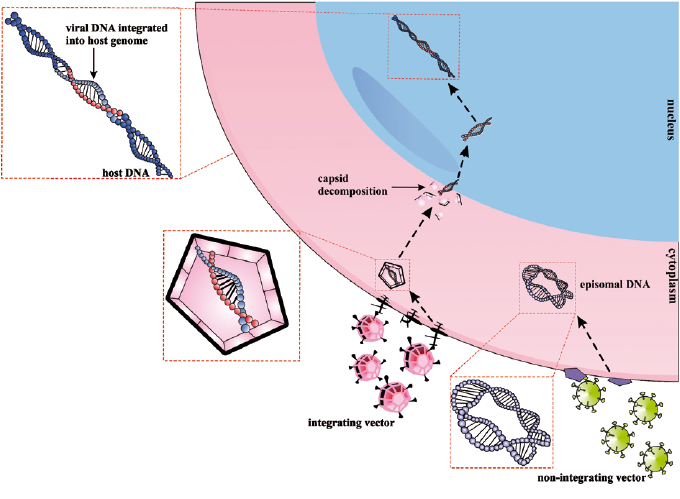

HPV

| Low-risk | High-risk |

|---|---|

| 良 | 惡 |

| episomal form | integrated form |

- E6 → p53, E7 → RB

episomal v.s. integrated form